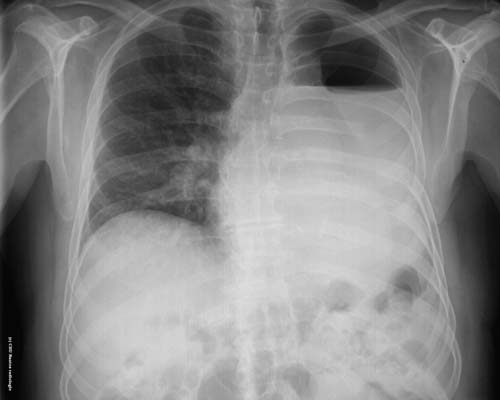

Hydropneumothorax

Opacité hydrique de l'hémithorax gauche avec un niveau hydro-aérique au 1/3 supérieur de l'hémithorax : épanchement mixte hydro-aériquede la grande cavité pleurale (hydro-pneumothorax )